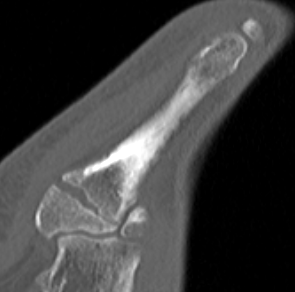

Zone 2 Jones fracture

- transverse fracture of 5th metatarsal shaft

- 1.5cm from base

- diaphysis / metaphysis junction

- extends into 4th / 5th metatarsal joint